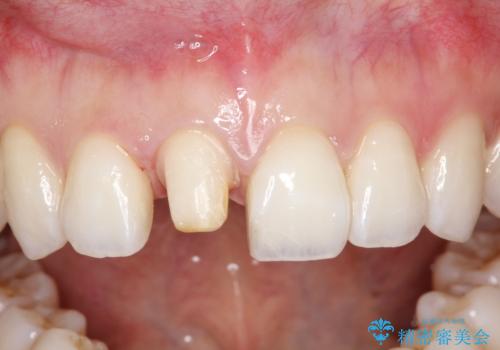

【オールセラミッククラウン】前歯の被せ物

- 矯正後、前歯被せ物のやりかえを希望され治療を行いました。

オールセラミック(スペシャル)にて修復しております。